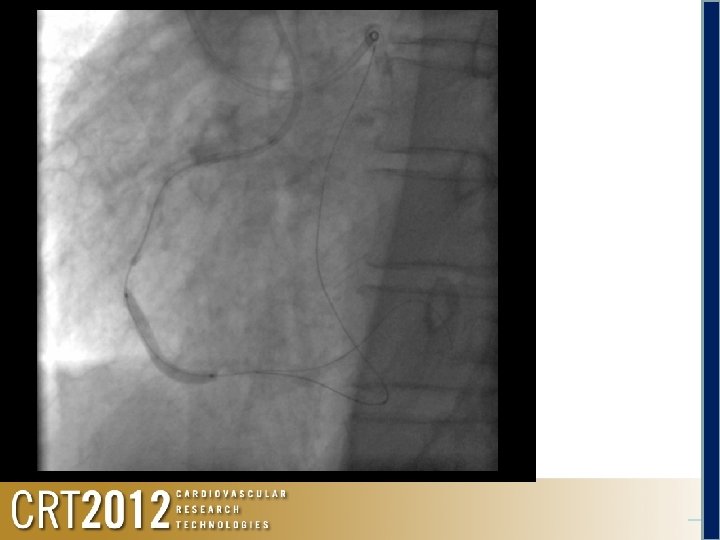

Antegrade Via the Rt. brachial 6 F SAL 1. 0 SH FINECROSS + Runthrough HC ↓ Not cross #2

Antegrade Anchoring at #1 by a Tazuna OTW 3. 0 mm oring h c n A Retrograde We repeated a dilatation at the occlusion site using a Tazuna 1. 25

r Ancho ing